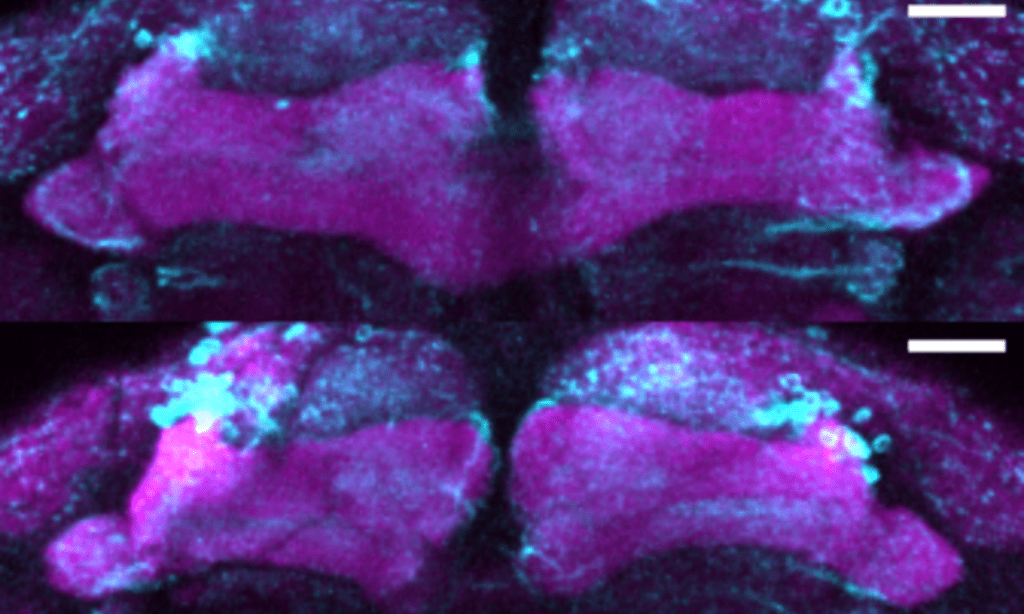

To investigate the mutation’s role, the researchers created a model using fruit flies that lacked the SGIP1 gene. These flies exhibited symptoms similar to those seen in Parkinsonism, including movement difficulties and brain cell degeneration. Closer examination revealed that the mutation caused defects in synapses, the structures that allow brain cells to communicate.

Further analysis showed that key structures in the synapses, responsible for recycling and breaking down proteins, were missing. This disruption suggests that the SGIP1 mutation interferes with the brain’s ability to maintain healthy synapses, which may play a significant role in the development of Parkinsonism.